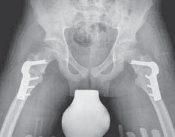

34. Once there is clinical and radiographic evidence of union and consolidation of the osteotomy, all restrictions can be lifted (

FIG 5

).

A

B

FIG 5 • Postoperative AP and lateral radiographs.

36. If adequate correction is achieved, ambulatory patients can expect to experience noticeable benefits in the appearance of their gait. Whether there are measurable functional improvements is less clear.